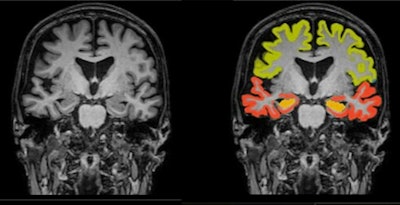

The grant from the foundation supports the development of a regulatory-cleared application to automatically analyze brain MRI scans to improve monitoring of Parkinson's disease (PD) patients during regular clinical treatment, as well as for patient selection and outcome assessment in multi center drug development trials, according to the company.

The company noted that it's collaborating with Kathleen Poston, MD, a professor of neurology and neurological sciences at Stanford Medicine. She heads a research project evaluating volumetric patterns of brain MRI scans and correlating these to corresponding clinical scores for motor and cognitive function, according to Icometrix.

Poston presented initial findings at the recent 2023 Alzheimer's and Parkinson's Disease Conference, showing that regional brain volumetry assessment can serve as an important biomarker in prediction and differentiation of PD patients at risk for motor and/or cognitive disability progression.